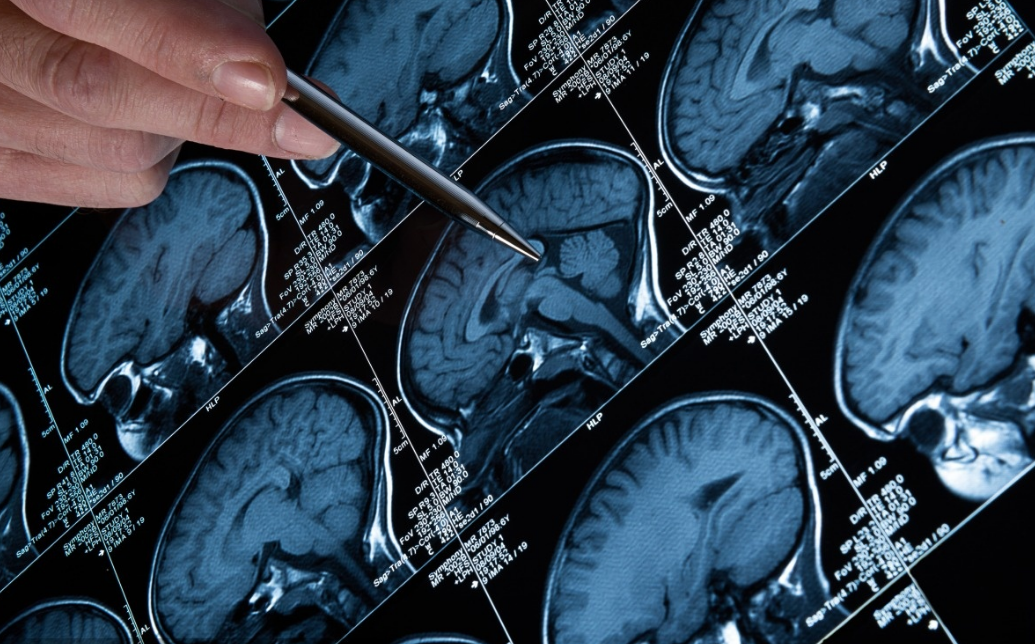

癫痫是一种由多种病因引起的慢性脑部疾病,是脑神经元过度放电导致反复、发作性和短暂性的中枢神经系统功能失常。临床表现为短暂感觉障碍,肢体抽搐,意识丧失,行为障碍或植物神经功能异常。长久以来人们对癫痫的认知误区,不但影响到患者、家属和社会,也影响着部分医务工作者。

干细胞是一类具有自我复制和多向分化潜能的细胞, 在一定条件下, 它可以分化成多种功能细胞, 具有再生人体各种组织器官的潜在功能, 医学界称为“ 万用细胞” 。干细胞进入人体后,通过引导神经细胞活化,促使脑部受损细胞进行DNA修复,重建神经网络,激发神经自身保护功能,完全恢复病灶区域神经功能,从而修复大脑内受损神经元。该疗法标本兼治,能建立健康脑环境,消除脑神经紊乱,使脑组织恢复健康活常态,帮助患者摆脱癫痫困扰。